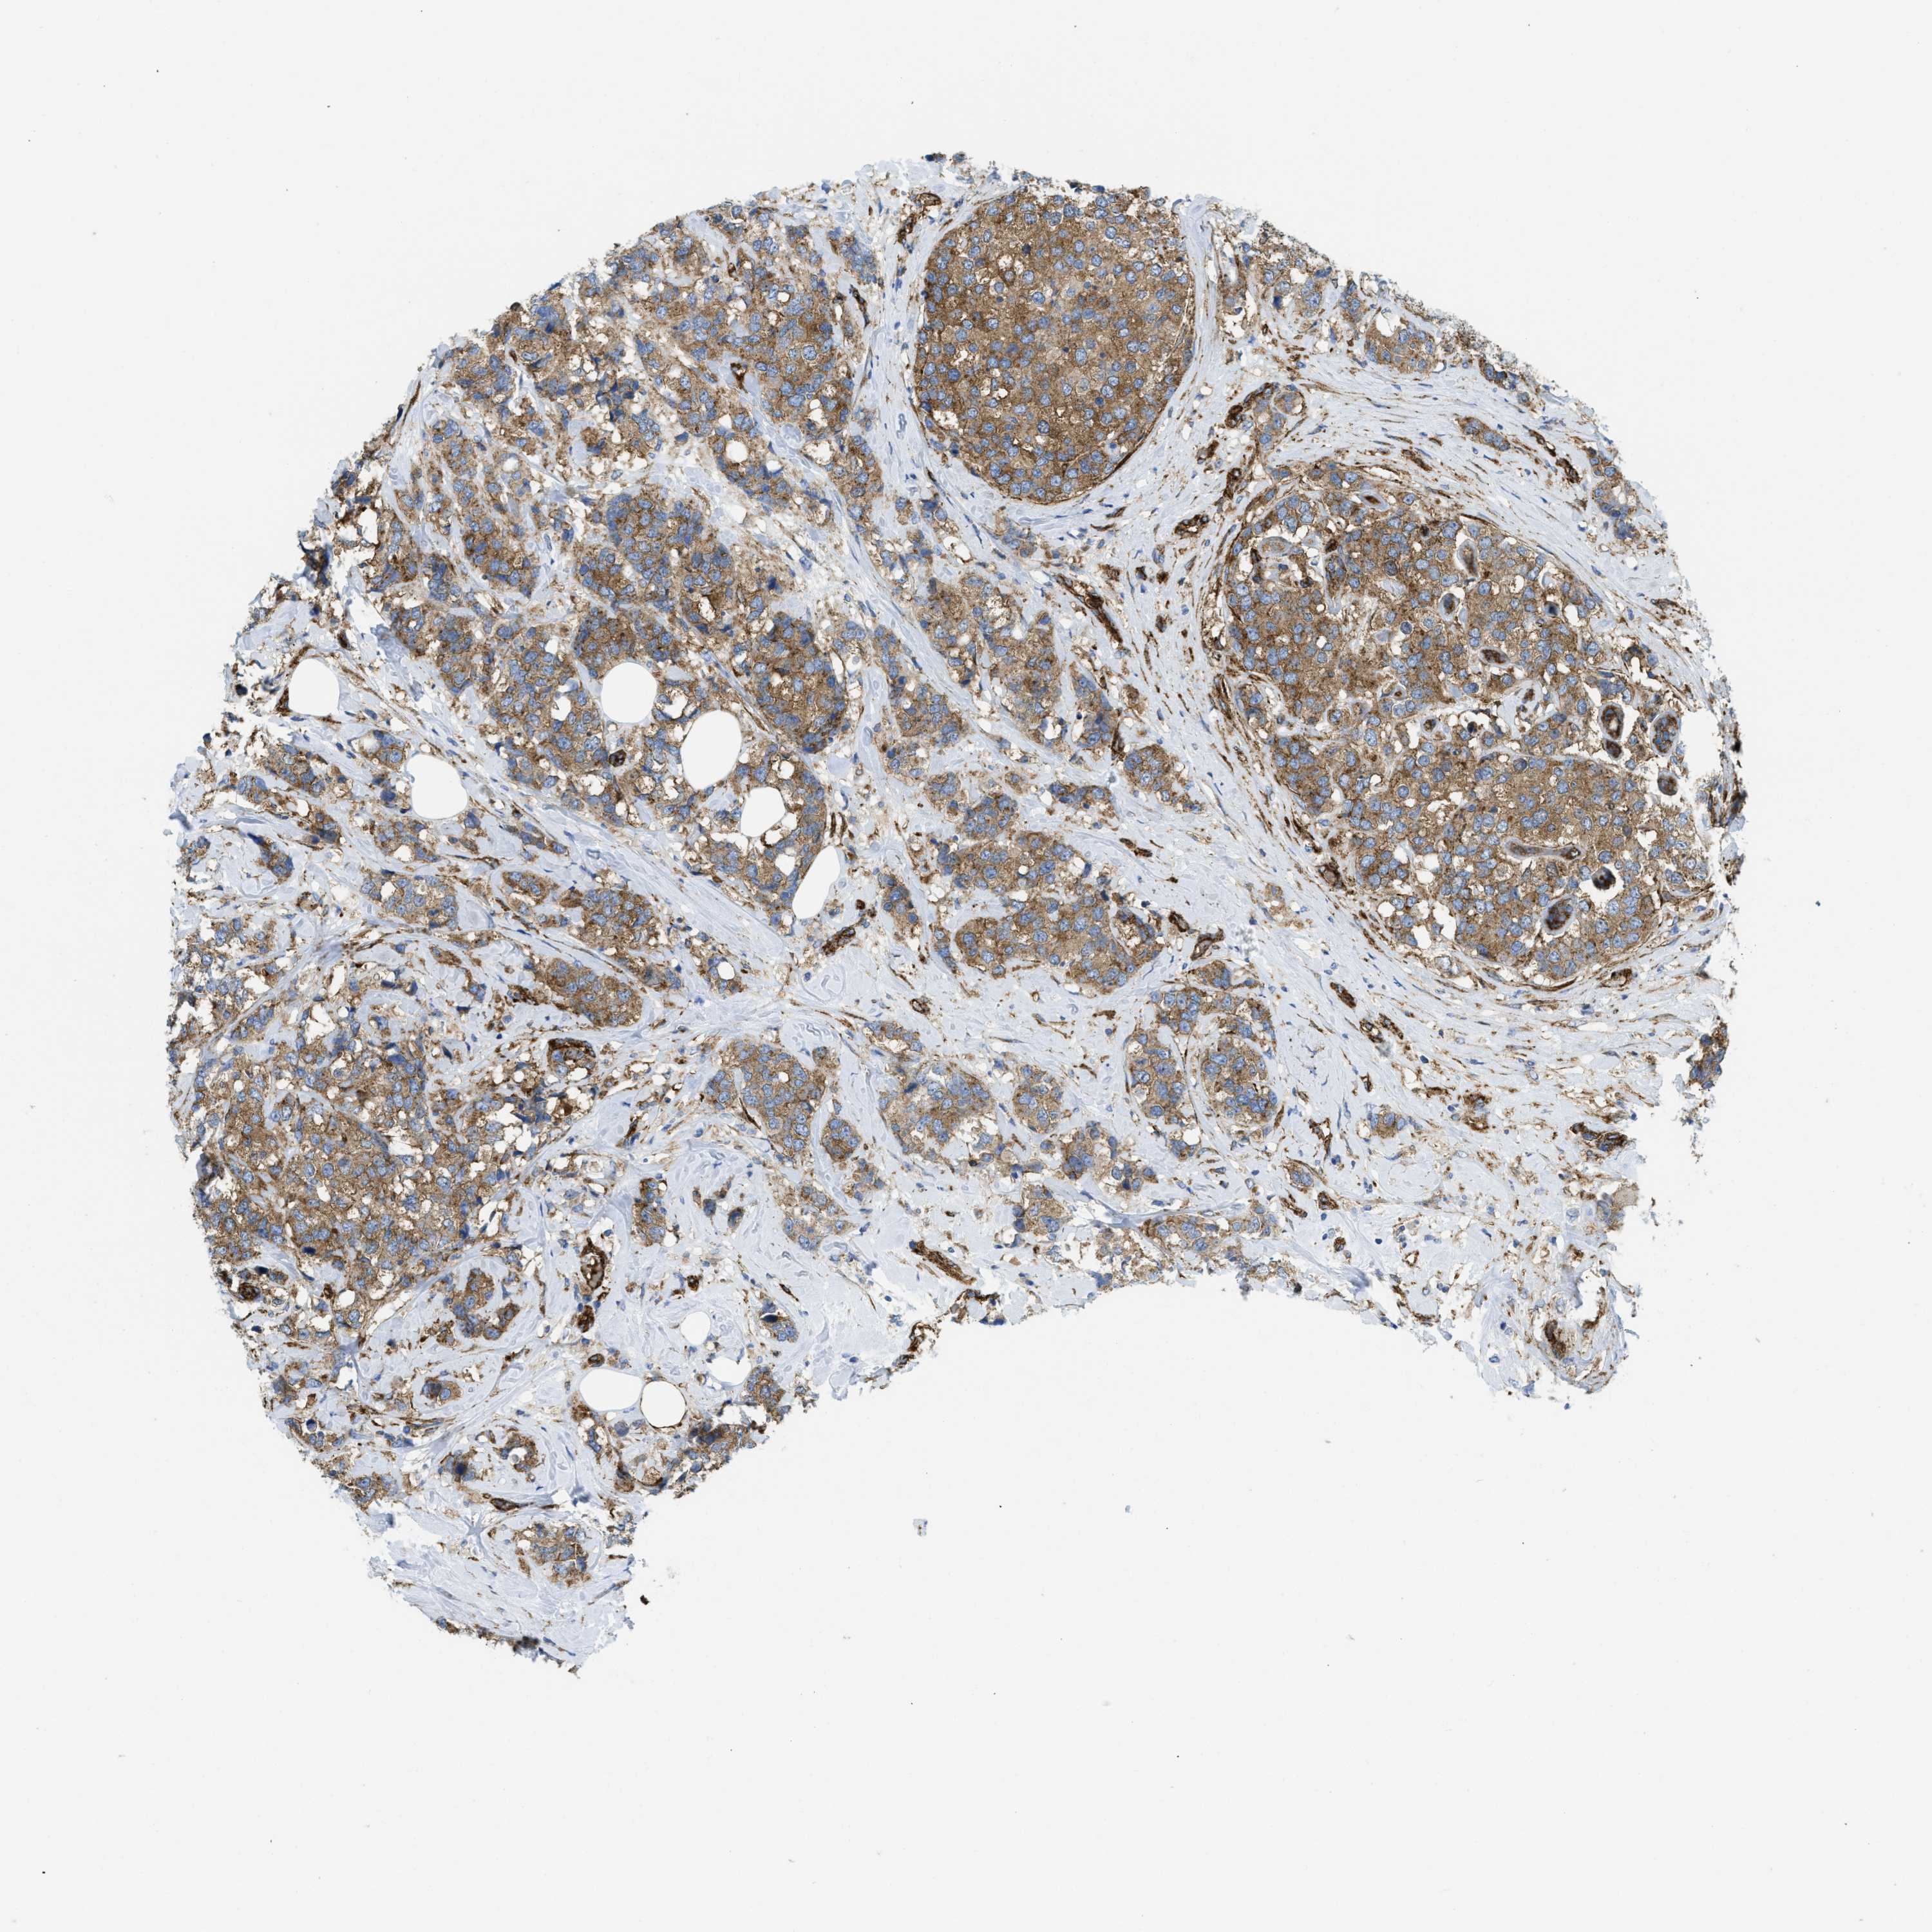

CANCER BREAST CANCER Show tissue menu

BRCA TCGA BRCA VALIDATION PROTEIN EXPRESSION

Breast cancer

Human cancer